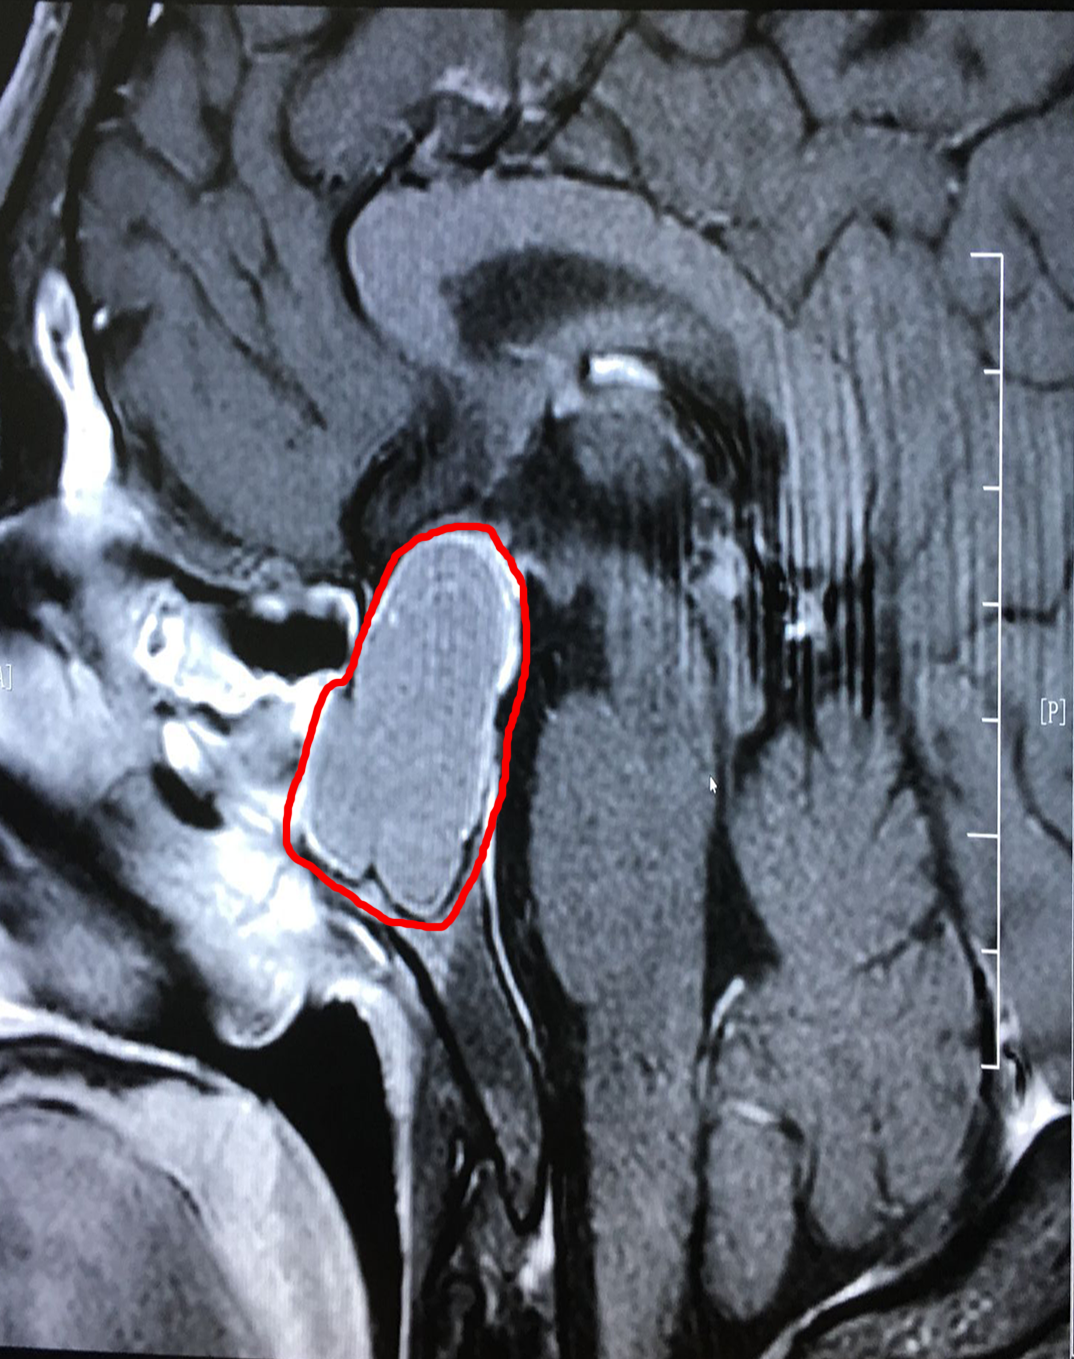

到院后,李士其教授和潘仁龙主任一起,研究讨论了患者病情:由于患者颅内鞍区的肿瘤很大(约1.8*3.1公分),已严重影响到患者的垂体功能,并压迫视神经,感觉神经等功能。李士其教授表示:手术是刻不容缓的事,待患者检查结果出来,没有手术禁忌,就可以立即实施手术。

术后第二天影像:肿瘤切除干净,鞍内脑脊液填充